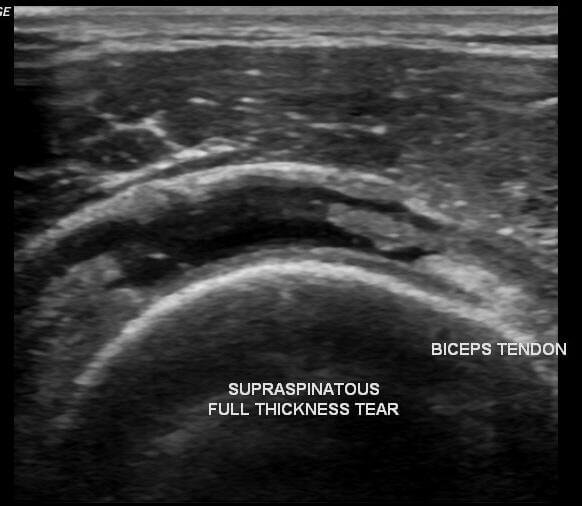

A full thickness tear of the supraspinatus tendon occurs when the rupture extends through the entire thickness of the tendon, creating a communication between the shoulder joint and the subacromial space.

These injuries are considered an advanced form of supraspinatus tendon tear and may vary in severity. They are often divided into:

- Incomplete full-thickness tear, where only a small part of the tendon is detached from the bone.

- Complete full-thickness tear, in which the tendon is fully detached from its insertion on the humerus.

- Ultrasound is commonly used as an initial imaging method because it allows dynamic assessment of the rotator cuff tendons and can reliably detect partial and full-thickness tears.